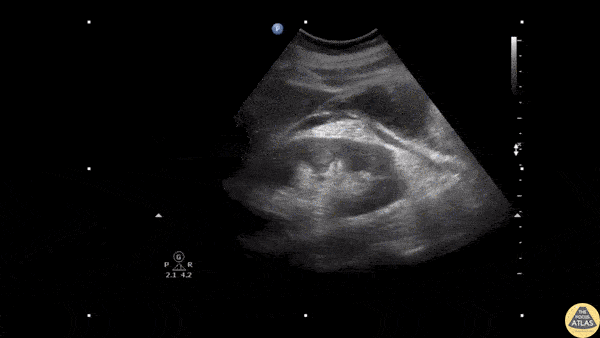

Bowel-GI - Retroperitoneal Hemorrhage

An elderly male presented to the ED with hypotension and abdominal pain. Ultrasound revealed retroperitoneal fluid in perirenal and anterior pararenal spaces. Image courtesy of Robert Jones DO, FACEP @RJonesSonoEM Director, Emergency Ultrasound; MetroHealth Medical Center; Professor, Case Western Reserve Medical School, Cleveland, OH View his original post here